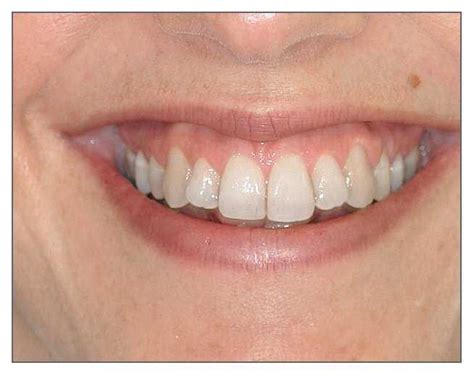

Una sonrisa estética o agradable está comprendida por tres componentes primarios: los dientes, el marco labial y la plataforma gingival. La sonrisa ideal, estética y agradable presenta las siguientes características:

- Mínima exposición gingival.

- Exposición simétrica y armónica entre la línea gingival superior y el labio inferior.

- Tejido gingival sano que rellena todos los espacios interproximales.

- Armonía entre los segmentos anterior y posterior (principio de graduación).

- Dientes con correcta anatomía y proporciones (forma y posición).

- Color y tono adecuado de los dientes.

- Labio inferior paralelo a los bordes incisales de los dientes anterosuperiores y a una línea imaginaria que transcurre por los puntos de contacto de estos dientes.